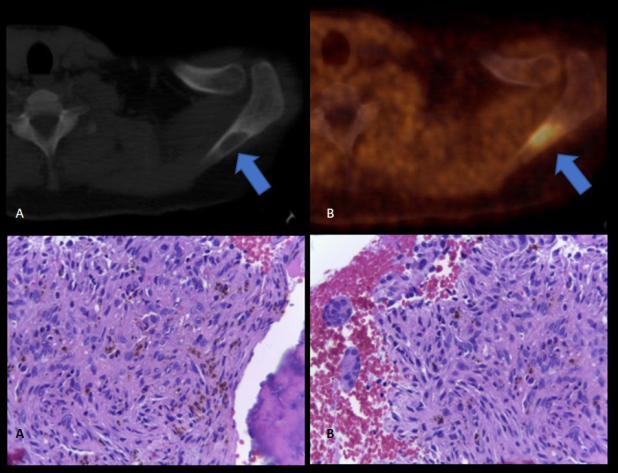

Paciente de 72 años con insuficiencia renal crónica en plan de trasplante, con cirugía previa de paratiroides. Por valores elevados persistentes de PTH y ante resultados confusos del centellograma con 99m Tc- sestamibi, se realiza PET-CT con 18F-Colina para detectar presencia de tejido paratiroideo hiperfuncionante. En el estudio híbrido morfo-molecular se evidencia imagen nodular de 17 mm en región ínfero medial cervical anterior con aumento de la captación del radiotrazador (SUV máx. 3,5) consistente con tejido paratiroideo (fig. 3). Además, se detecta una lesión predominantemente lítica e hipercaptante de 26 mm de diámetro en la espina del omóplato izquierdo, que cursaba en forma asintomática (fig. 4, arriba). Se realiza biopsia de la misma, dando como resultado tumor pardo (fig. 4, abajo).

El caso número 2 se trata de un paciente sometido a un estudio morfo-metabólico PET-CT con 18F-Colina pre trasplante renal, indicado para descartar presencia de tejido paratiroideo hiperfuncionante ante la sospecha de hiperparatiroidismo terciario, siendo la lesión lítica en omóplato un hallazgo cuya posible etiología oncológica debía ser descartada. La colina forma parte de los fosfolípidos de la membrana celular, resultando ser la 18F-Colina un excelente biomarcador de proliferación celular. Su captación se encuentra incrementada debido a la sobreexpresión de la enzima colina quinasa, como se ha visto en patología oncológica prostática y en el tejido paratiroideo hiperfuncionante(3).